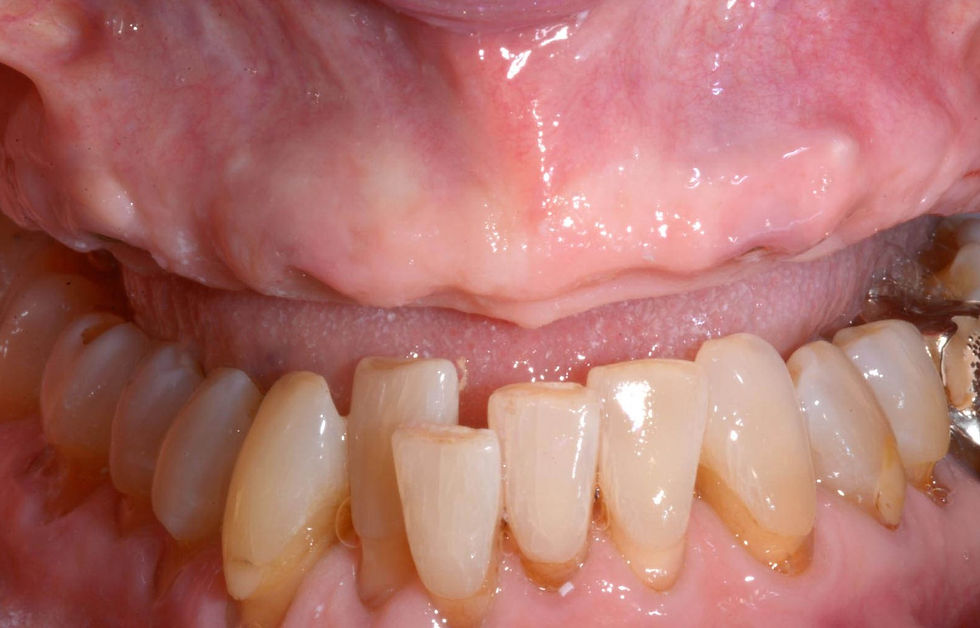

Clinical pre-operative intraoral images that show the vestibular migration of the natural teeth.